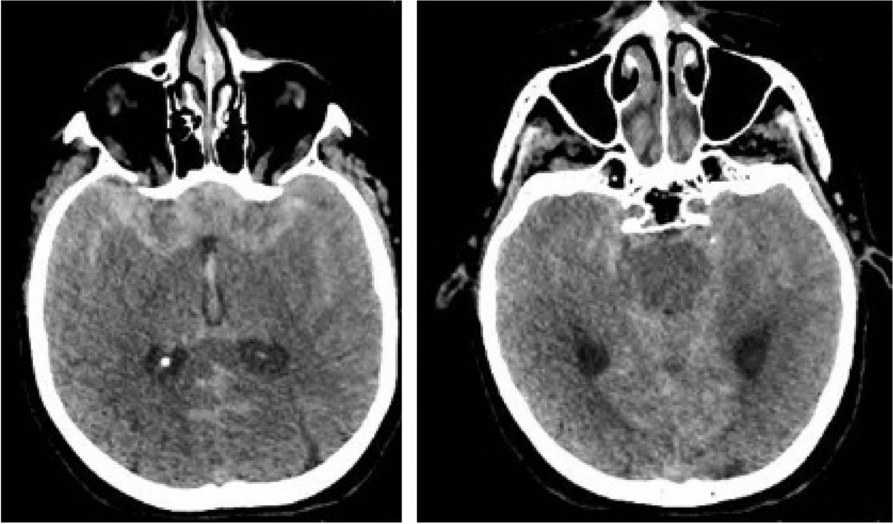

In this specific case, the patient, affected by L. Pneumophila, presented a PO2/FiO2 ratio between 100mmHg and 200mmHg, giving rise to a moderate ARDS panel according to Berlin Criteria (Image 1).

For this reason, we decided to use a non-invasive periprocedural ventilation mode, specifically the High Flow Nasal Cannula (HFNC), to reduce the risk of postoperative pulmonary complications due to invasive ventilation through endotracheal intubation (ETI).

Image 1 (abstract A9).

See text for description